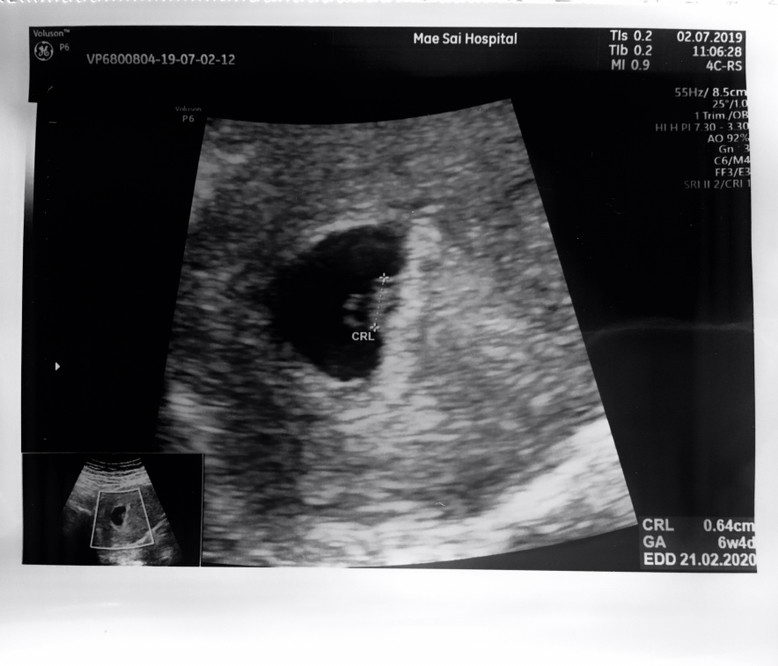

ท้องได้9สัปดาห์แล้วค่ะ แต่หมอยังไม่ซาวด์ให้เลย อยากทราบว่าคุณหมอซาวด์ให้ตอนกี่สัปดาห์คะ อยากเห็นค่ะว่าเค้าเป็นยังไงบ้าง